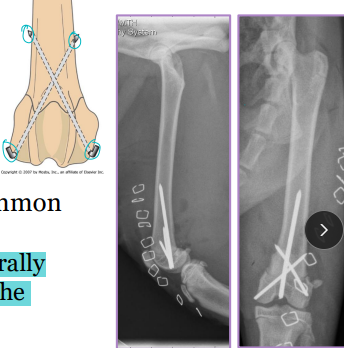

Radius & Ulna Fractures

Considerations: No soft tissue envelope, weight-bearing, blood supply poor in small breeds, poor healing, Robert/modified jones bandage

Tx: rigid fixation, often only radius tx

Bone plate & screws (#1)

IM pins contraindicated for radius

IM pins NOT in radius (cats need both)

JUST the radius in fixed(dogs)

External skeletal fixation→ open fractures, 1A ESF

Casting: acceptable if 50% reduction; best for transverse fractures in young dogs

NOT in toy breeds